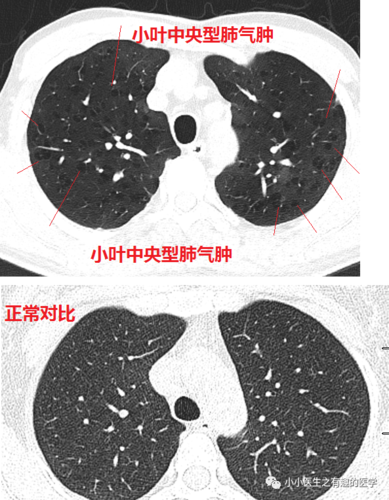

ct经典图谱:肺气肿ct典型图谱,一学就会